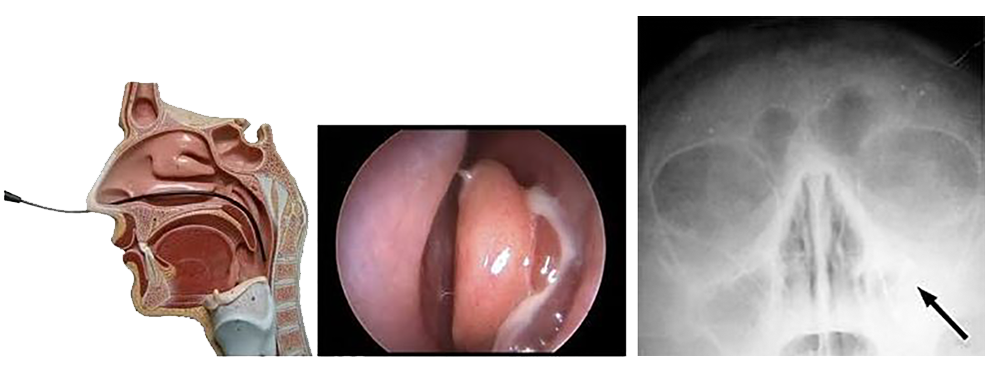

! ДИЈАГНОЗА

! Дијагнозата кај синузитите се поставува врз основа на:

1 детална анамнеза

2 комлетен оториноларинголошки преглед

3 флексибилна / фиберназофарингоскопијa – оваа дијагностичка метода овозможува многу попрецизна евалуација на носните простори. Таа ни дава податоци во однос на промените на носната лигавица / пребоеност, оток, хипертрофија, деформитет / девијација на носната преграда, присуство на секрет и локалнизација, проценка на третиот крајник кај децата, носни полипи и други состојби што се важни во проценката на синусните инфекции.

4 ртг снимка на синуси или КТ на параназални синуси